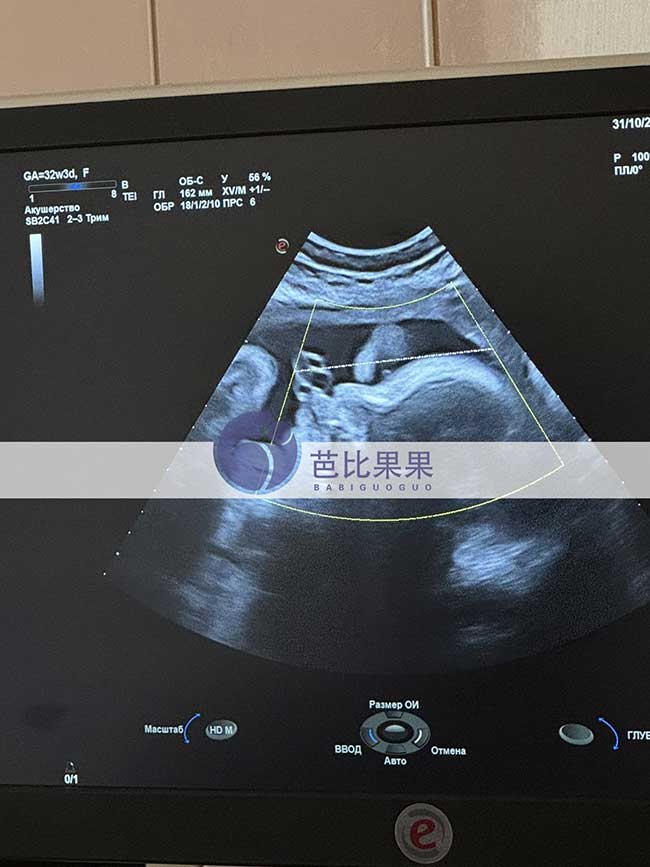

杨先生再次到乌克兰生娃匹配的试管妈妈来医院做B超啦,已经孕32周,胎宝宝发育的很好,试管妈妈状态也棒棒的